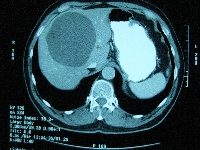

Ασθενής 61 ετών ο οποίος, στα πλαίσια διερεύνησης επιγαστραλγίας, διαπιστώθηκε ότι έπασχε από ευμεγέθη (13 cm) επικρατούσα απλή ηπατική κύστη που εδράζονταν στα ηπατικά τμήματα 4α, 5, 7 και 8 (εικόνα 1). Η κύστη παρεκτόπιζε μερικώς το δεξιό κλάδο της πυλαίας φλέβας (εικόνα 2) και εφάπτονταν με τη δεξιά ηπατική φλέβα (εικόνα 3). Ο ασθενής υποβλήθηκε σε λαπαροσκοπική (HALS) μαρσιποποίηση της ηπατικής κύστης (εικόνα 4) κατά την οποία αφαιρέθηκε > 50% του άνω και οπισθίου τοιχώματός της, μαζί με τμήμα του παρακείμενου ηπατικού παρεγχύματος (εικόνα 5). Η ταχεία ιστοπαθολογική εκτίμηση του παρασκευάσματος δεν ανέδειξε κακοήθη στοιχεία. Επιπλέον, πραγματοποιήθηκε και επιπλοοπλαστική, ύστερα από πλήρη κινητοποίηση του μείζονος επιπλόου, μεταφορά του στο δεξιό υποδιαφραγματικό χώρο και τοποθέτησή του μέσα στην υπολειμματική κυστική κοιλότητα (εικόνα 6). Ο ασθενής έλαβε εξιτήριο την 4η μετεγχειρητική ημέρα. Έκτοτε παραμένει ελεύθερος συμπτωμάτων.